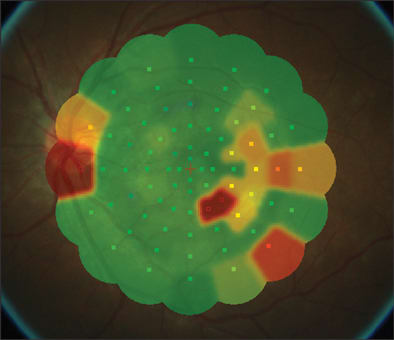

On initial exam, his vision was 20/25 in both eyes, anterior segment was benign and there was no evidence of vitreal cell. Inferiotemporal to the fovea of his left eye, he had a hypopigmented lesion deep to the retinal vessels (Figures 1A and 1B). On fluorescein angiography (FA), the hypofluorescent lesion appeared to be a cluster of hyperfluorescent dots (Figure 2), which were more apparent than on clinical examination. These dots appeared to stain slightly during late-phase angiography (Figure 3). Early-phase indocyanine green angiography (ICG) was unremarkable; however, during late-phase angiography, there were small hypofluorescent dots overlying larger hypofluorescent spots (Figure 4). There was also a lacy, irregular ring of hypofluorescence at the margin of the optic disc. The hypofluorescent spots appeared more numerous than was apparent on either fluorescein or on clinical exam. Microperimetry was performed. The imaged blind spots on microperimetry (Figure 5) corresponded to the hypopigmented areas noted on ICG. One week after the initial visit, multiple hyperfluorescent white dots appeared on the FA (Figure 6); during this visit, the patient had vitritis that resolved spontaneously within a few days. Repeat microperimetry (Figure 7A) and ICG (Figure 7B) showed improvement 6 weeks after the initial visit and after a course of steroids. Imaging supports a diagnosis of multiple evanescent white dot syndrome (MEWDS). RP

Figure 5. "Blind spots" on microperimetry that parallel the hypopigmented areas noted on ICG.

Figure 7A and B. Microperimetry and ICG taken 6 weeks after the initial visit and a course of steroids. The "blind spots" appeared to be resolving on microperimetry, which corresponded to an improved ICG.